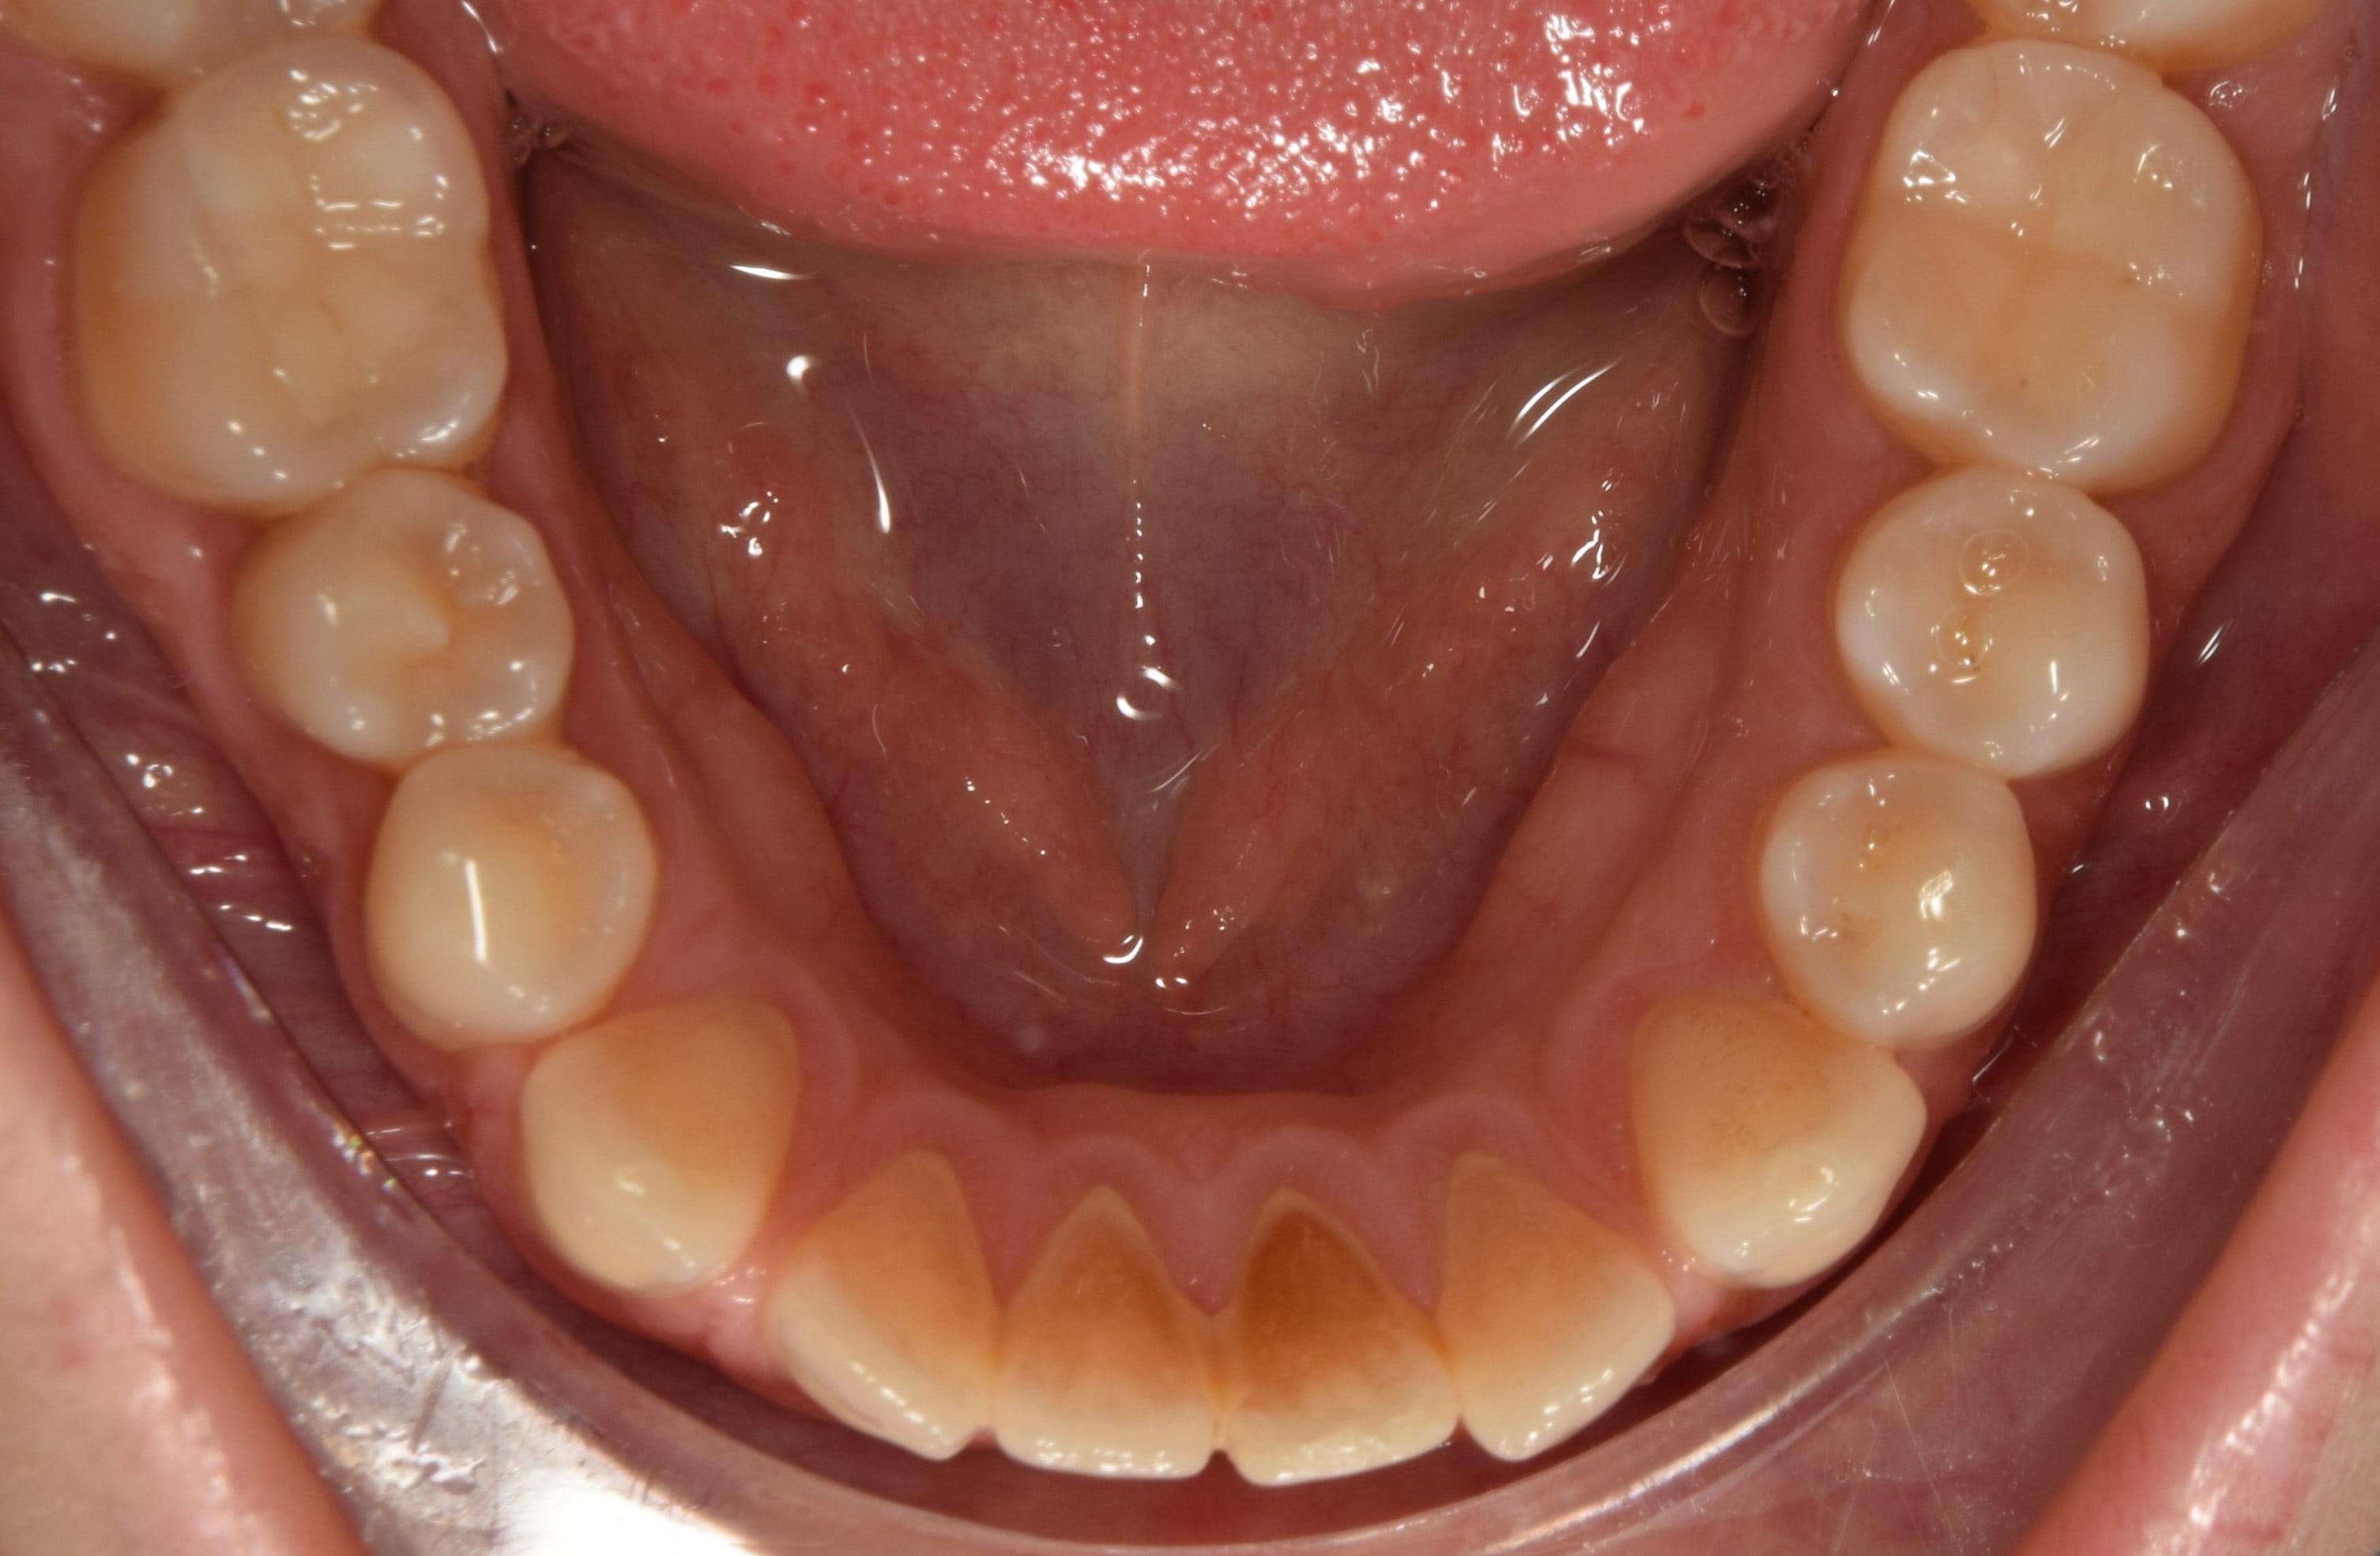

Korai vegyesfogazat

7-8 éves kor körül a gyermekek többségének korai vegyesfogazata van. Ez azt jelenti, hogy az első maradó nagyőrlők előtörtek, a tej metszőfogakat pedig felváltották a maradó metszőfogak.

Késői vegyesfogazat

10-11 éves korban beszélünk késői vegyesfogazatról, amikor megkezdődik az oldalsó tejfogak elvesztése, és a tej őrlők, tejszemfogak helyére nőnek a maradó kisőrlők és szemfogak. Késői vegyesfogazatban a szájüregben eltérő sorrendben nőnek a maradófogak, illetve esnek ki a tejfogak.